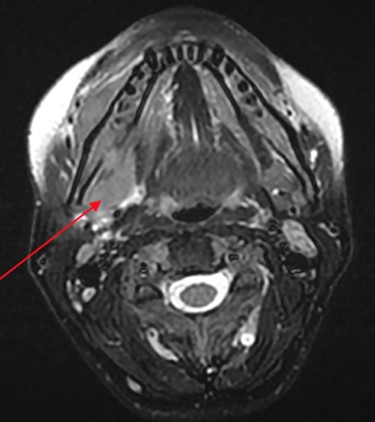

At her OMFS appointment, the consultant was concerned by the abnormal appearance of the extraction site intraorally, combined with the evolving systemic symptoms (Figs 2–4). Urgent magnetic resonance imaging (MRI) head and neck (Figs 5 and 6) and computerized topography (CT) mandible scans were requested and completed in an extremely short time frame.

MRI head (axial view) showing Burkitt’s infiltrating the mandible and oral mucosa.